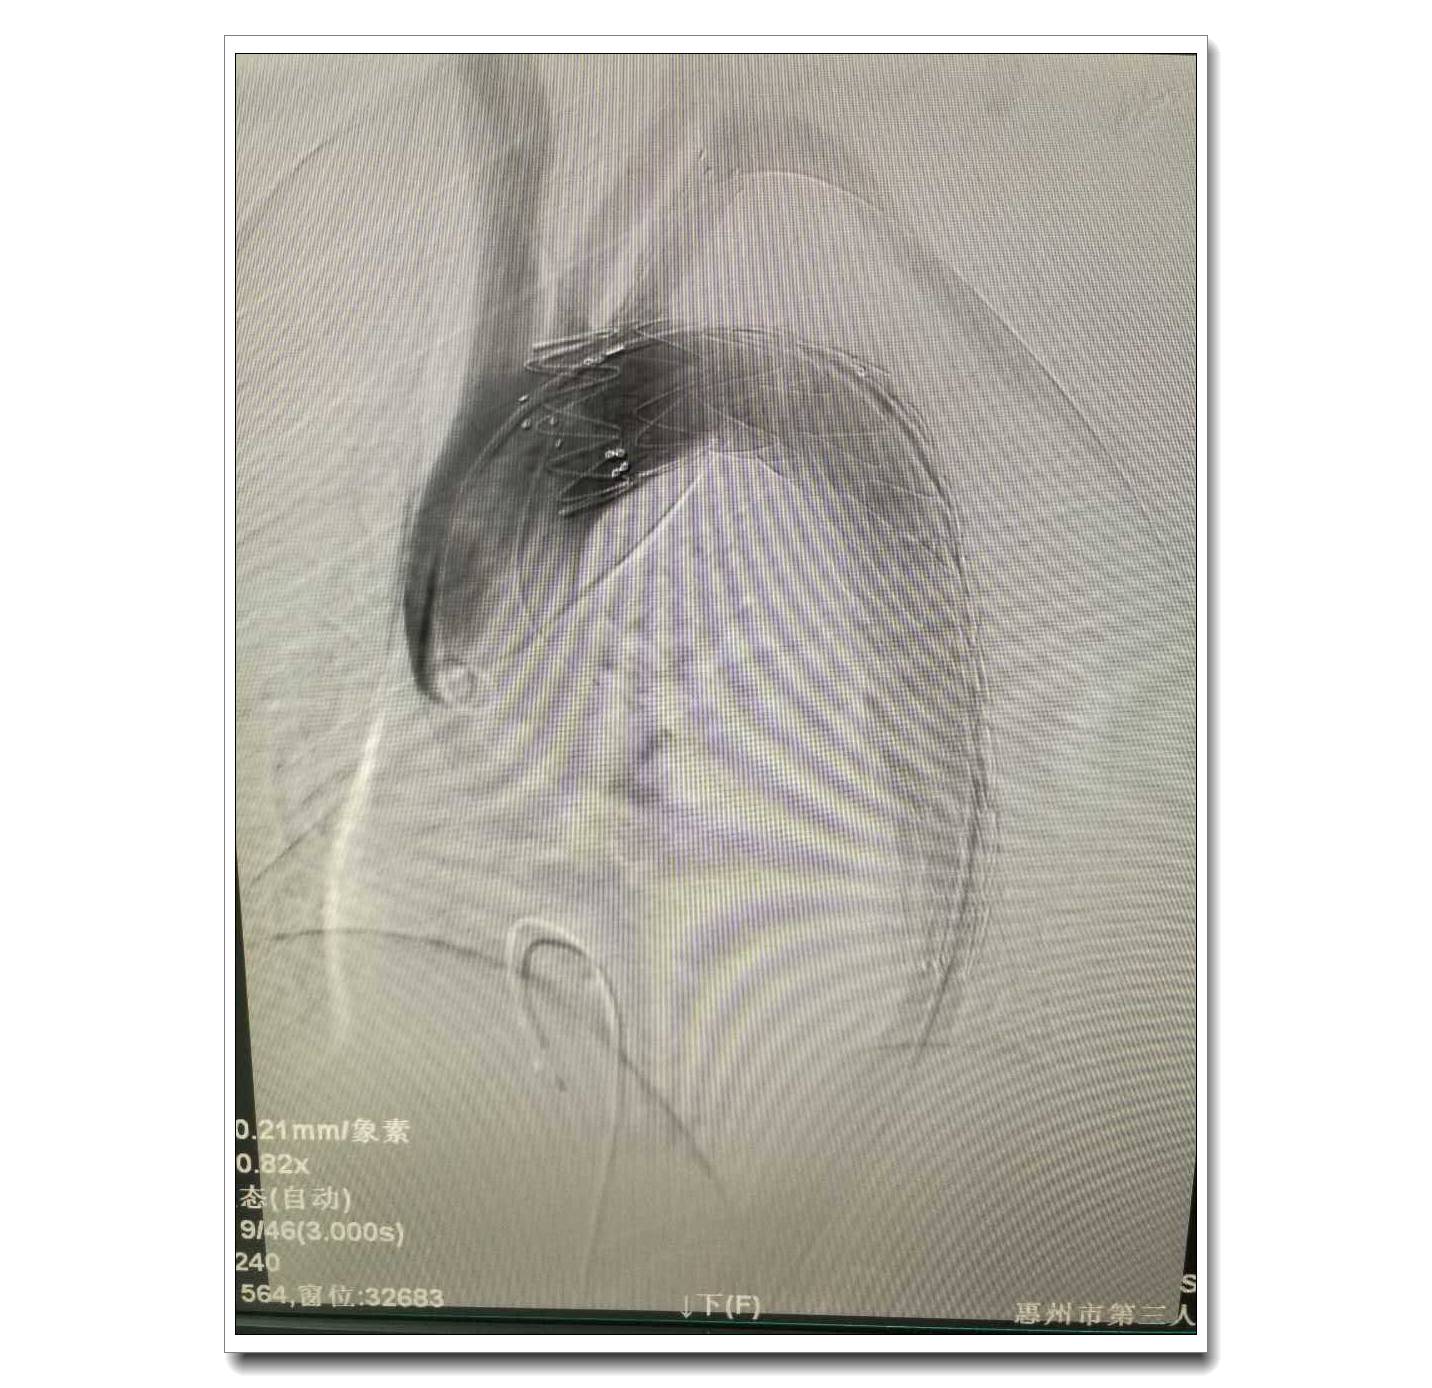

患者植入支架后主動脈造影圖片

生死競速!經(jīng)過術(shù)前精心的準備,在肖純副院長親自指導(dǎo)下,在心臟重癥監(jiān)護室及DSA室護理團隊的默契配合下,由鐘思干主任、廖火城主治醫(yī)師、劉建平主治醫(yī)師組成的手術(shù)團隊,以嫻熟的手術(shù)技巧,用了近70分鐘順利完成了主動脈夾層腔內(nèi)修復(fù)術(shù)以及左鎖骨下動脈重建術(shù),夾層破口被成功隔絕!手術(shù)成功了!